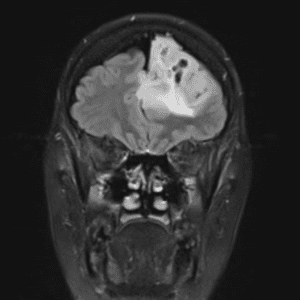

Case #11

Medulloblastoma